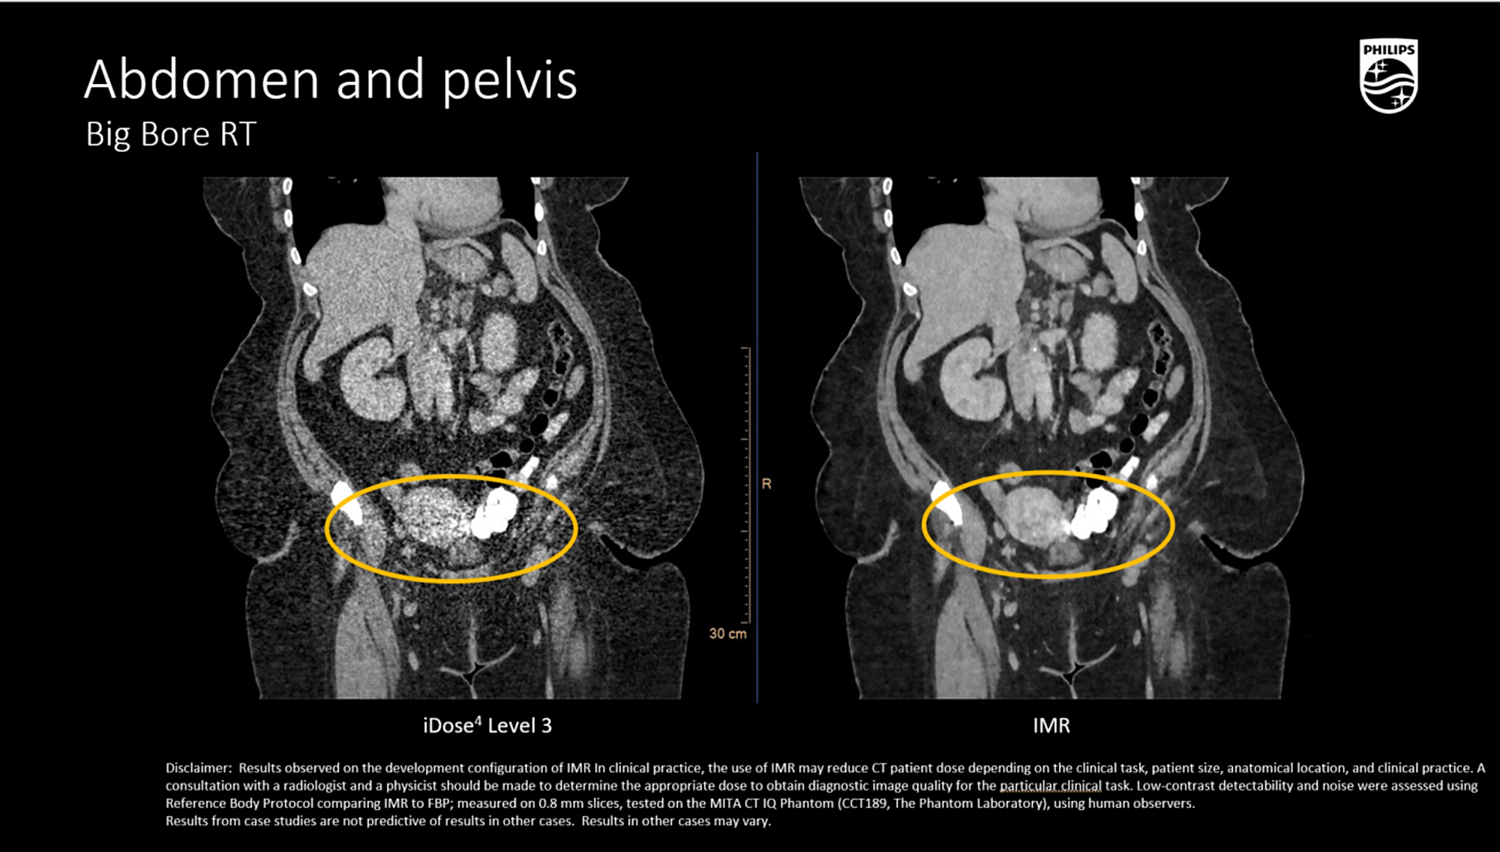

iDose⁴ (Iterative Dose Reduction Technology)

- Гибридная итеративная реконструкция в проекционном и изображен ческом пространстве повышает качество изображения и устраняет артефакты.

- Повышает контрастно-шумовое соотношение (CNR), снижая лучевую нагрузку на 50–80% при сохранении пространственного разрешения

Абдоминальная и тазовая локализация

- Визуализация мягкотканных опухолей (печень, почка, поджелудочная железа, органы таза) с контурированием OAR,

- Возможность КТ-анализов с контрастированием в артериальную, венозную и позднюю фазы,